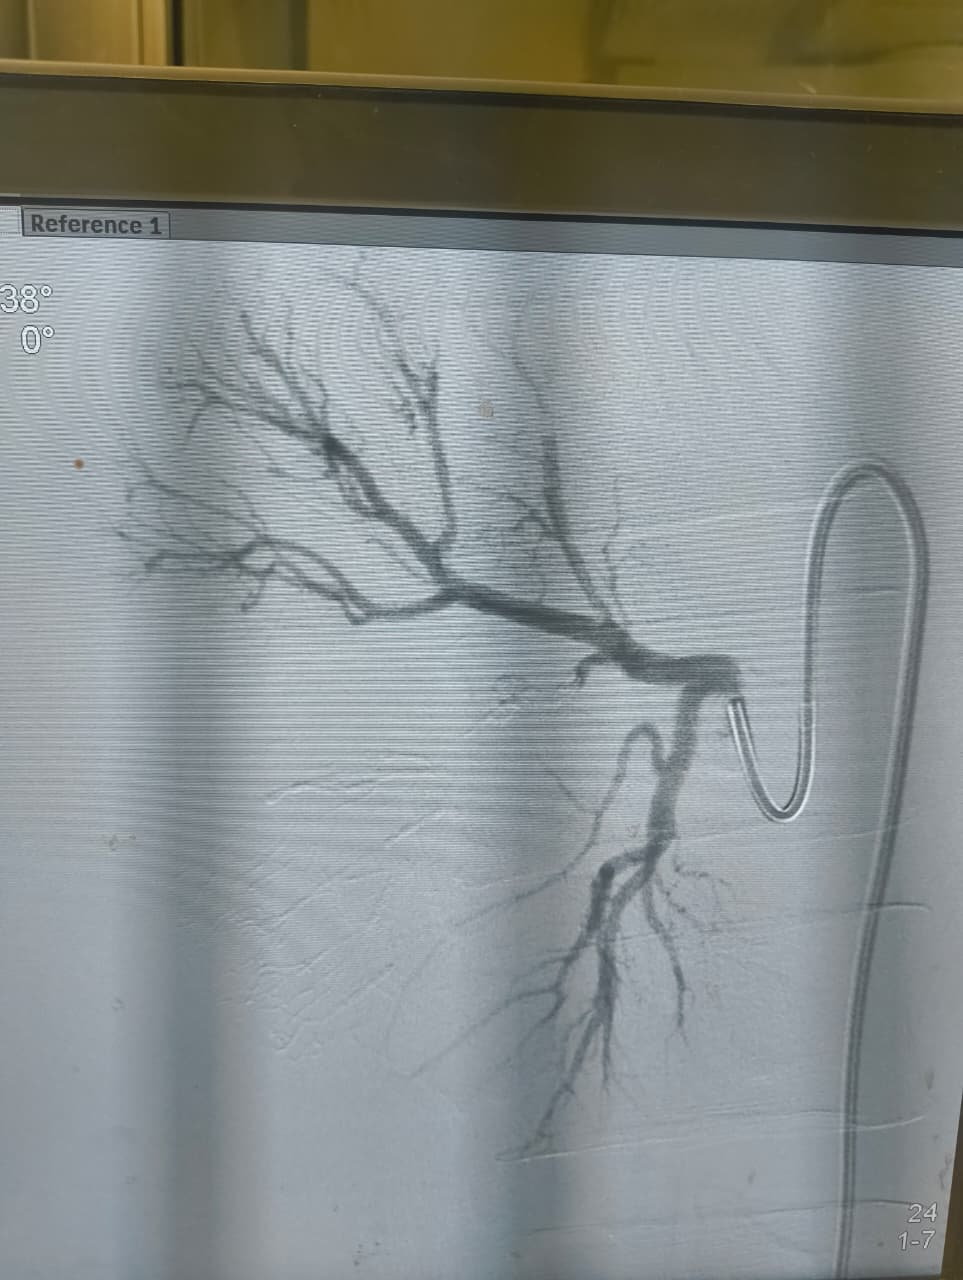

نجح الفريق الطبي بوحدة الأشعة التداخلية في إنقاذ شاب مصاب تعرّض لحادث أدى إلى قطع جزئي في الشريان الكلوي الأيمن مصحوبًا بتجمع دموي كبير خلف الغشاء البريتوني، وذلك دون اللجوء إلى استئصال الكُلى أو التدخل الجراحي التقليدي.

وتمكن فريق وحدة الأشعة التداخلية برئاسة الدكتور محمود غلاب، أستاذ الأشعة التداخلية بطب كفر الشيخ، من إجراء تدخل طارئ ناجح، تم خلاله سد التمدد الشرياني مع الحفاظ الكامل على التغذية الدموية لباقي أنسجة الكُلى، وهو ما يُعد من أبرز وأهم مميزات الأشعة التداخلية.